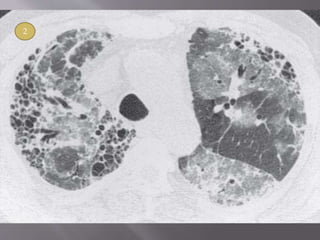

1. Marked fibrosis- On HRCT, IPF is characterized by

intralobular interstitial thickening , results in

reticular pattern in subpleural region - typical

pathological feature of UIP. Dilated and distorted

centrilobular bronchioles are frequently visible

within the areas of reticulation, i.e., traction

bronchiolectasis.

2. Honeycombing- Honeycombing is critical for

making a definitive diagnosis on HRCT,

individual lobules are no longer visible.

Honeycomb cysts usually range from 3 to 10

mm in diameter, but they can be as large as 2.5

cm. The frequency of honeycombing varies

with the severity or stage of the disease.

Findings of honeycombing and fibrosis are

most often symmetric.

3. Patchy involvement- Areas of mild and severe

fibrosis and normal lung are often present in

the same patient, in the same lung, and in the

same lobe.

 A confident diagnosis of IPF on HRCT requires clinical

exclusion of known causes of UIP and the presence of all of

the following four criteria: reticular pattern, honeycombing,

subpleural and basal predominance, and absence of atypical

features.